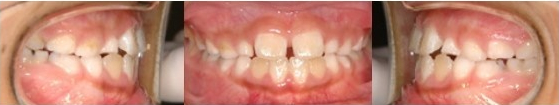

Pre-Ortho type 3. 반대교합 전용

8세남아 프리올소 착용 3개월 후

마지막 반대교합 전용 타입입니다.

교합을 맞물렸을 시 아랫니가 윗니를 덮은

상태이지만 이 프리올소로 거꾸로 물린 증상을

회복해 정상교합으로 도와주게 됩니다.